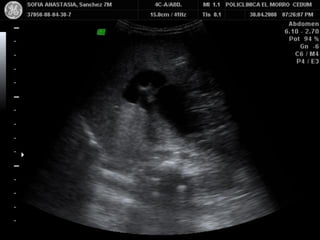

BARRO BILIAR

HEMORRAGIA VESICULAR

CARCINOMA VESICULAR

MATERIAL SIMILAR A TEJIDO

BLANDO INTRAVESICULAR

• AYUNO CRONICO/COLECISTITIS

•

ACALCULOSA.

OBSTRUCCION VESICULAR

HEMORRAGIA VESICULAR / DETRITUS

POR INFECCION.

POLIPOS VESICULARES

CARCINOMA / METASTASIS

LITOTRIPSIA EXTRACORPOREA

ARTEFACTOS.